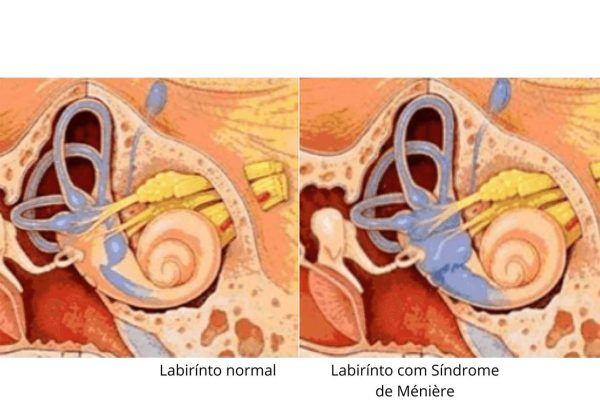

A doença de Ménière é um distúrbio caracterizado por ataques recorrentes de vertigem incapacitante (uma sensação falsa de movimento ou giro), perda de audição flutuante (nas baixas frequências) e barulho no ouvido (acufeno).

Os sintomas incluem súbitos ataques não provocados de vertigem incapacitante severa, náusea e vômito, geralmente seguidos de sensações de pressão no ouvido e perda da audição.

A doença de Ménière, também chamada de hidropisia endolabiríntica, é uma doença do ouvido interno que afeta a audição e o equilíbrio.